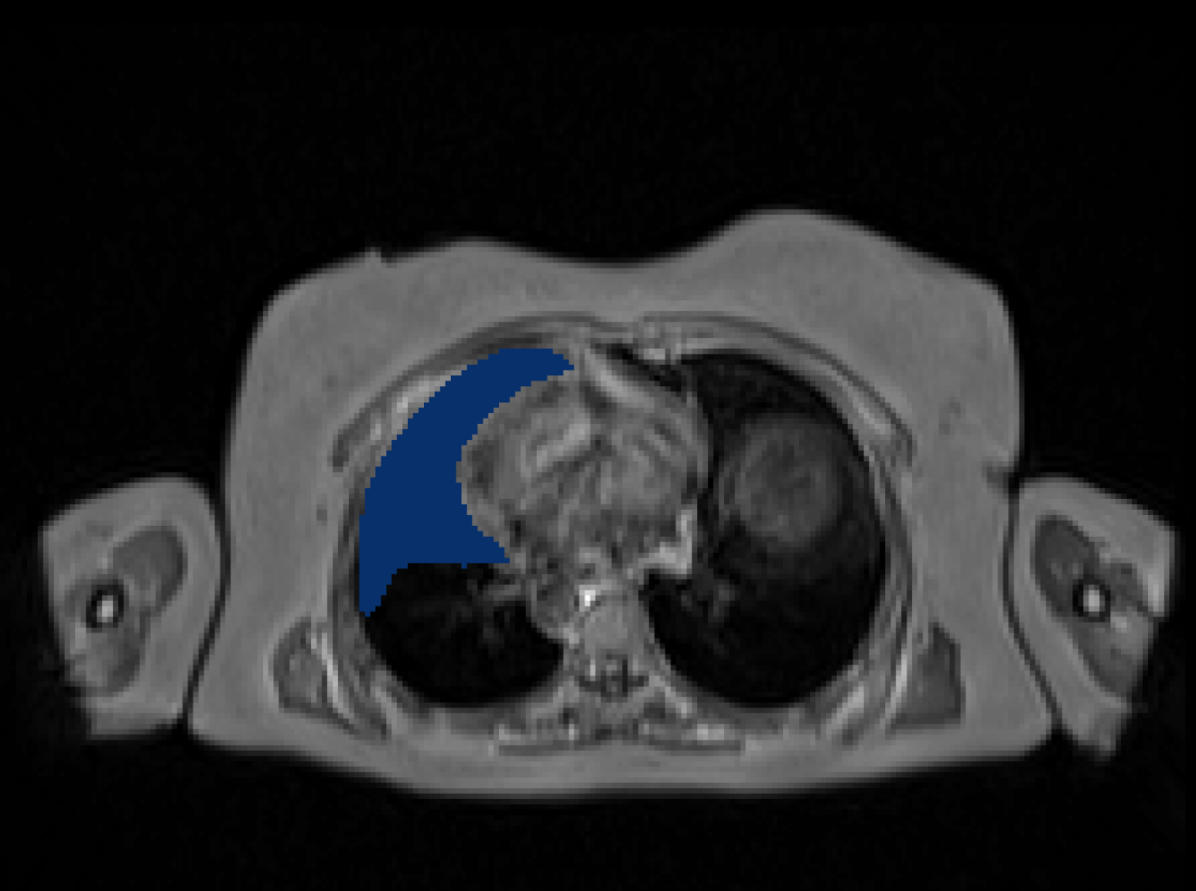

3.3 Entropy Test-Time Adaptation (ETTA)

A common practice in medical imaging to addresses the labels distribution-shift is to employ Test-Time Adaptation (TTA) by fine-tuning model parameters at test time using only test data without ground-truth [33]. To mitigate the impact of any residual label noise at UKBOB, we introduce Entropy Test-Time Adaptation (ETTA). ETTA refines the model’s predictions on test samples by fine-tuning the batch normalization parameters using the test data itself, guided by minimizing the prediction entropy. Given a test sample , we first obtain the network’s initial prediction , where is the softmax probability over classes at each of the voxels in the sample. Here, represents the segmentation network parameterized by . We define the entropy loss over the predicted probabilities:

where is the probability of class at voxel .

We update only the batch normalization parameters while keeping the other network parameters frozen (see pipeline in Figure 4). The adaptation process involves minimizing the entropy loss with respect to :

| (3) |

This process adapts the model to the test sample by encouraging confident (low-entropy) predictions, thereby refining the segmentation output. The adaptation is efficient as it involves updating a small subset of parameters and can be performed online during inference. ETTA leverages the entropy of the network’s predictions (Figure 5) to guide the adaptation, improving robustness to domain shifts and label noise.